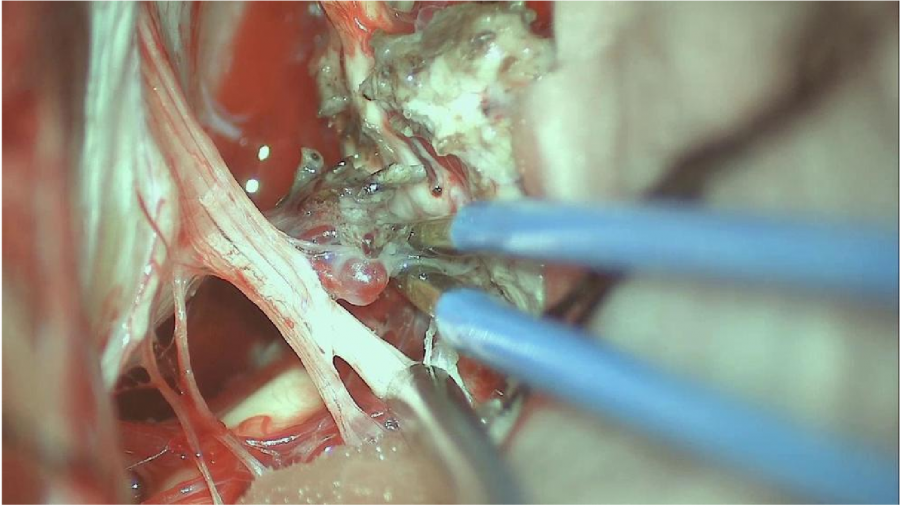

⾏左侧远外侧⼊路脑⼲⾎管畸形切除术,术中所⻅:

3、脑⼲动静脉畸形⼿术切除是注意辨别供⾎动脉与引流静脉,其往往不似其他部位的动静 脉畸形,有叫粗⼤的引流静脉。术中如果不能辨清各⾎管来源与去处,往往会造成不可估量的损失。

4、脑⼲动静脉畸形团周围玩个昂存在复杂的神经及⾎管,操作难度⼤。